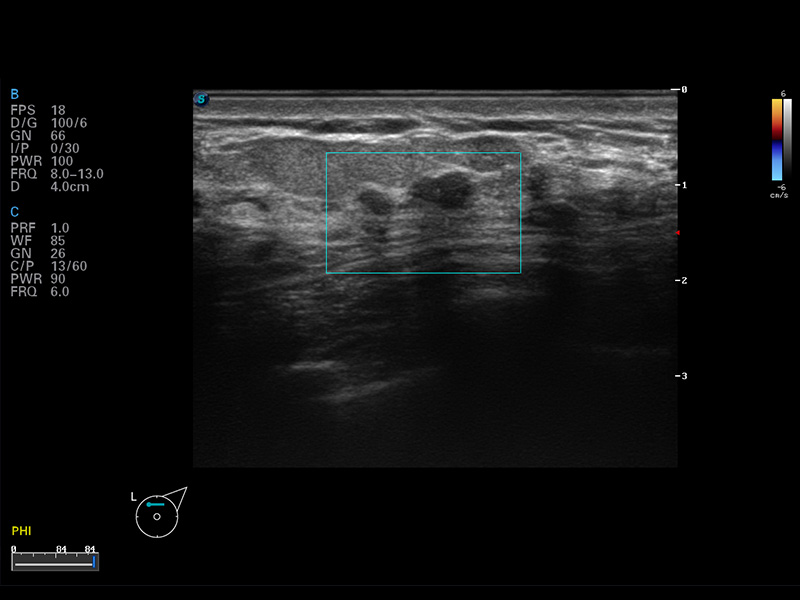

S8 EXP便携式彩色多普勒超声诊断仪是美狮贵宾会官网研发的高端全身应用型便携彩超。高通道的VIS平台融合可视化(Visual)、智能化(Intelligent)和人性化(Smart)的特点,配以美狮贵宾会官网自主研发生产的探头大家族,使您能够快速、准确的获得病人信息,提高工作效率的同时减轻疲劳。